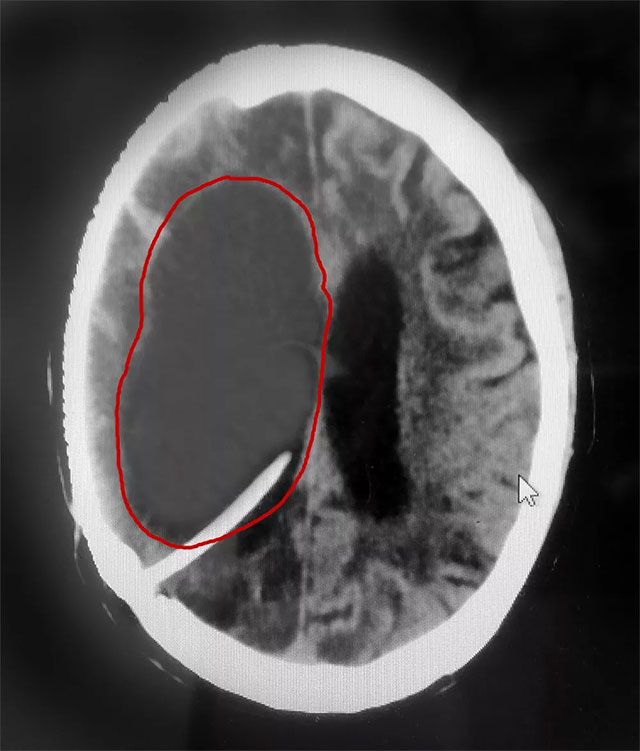

近日,上海藍十字腦科醫(yī)院神經(jīng)外科6A病區(qū)收治了一位重度腦積水患者。三年前,患者金某(化名)因右側(cè)大腦中動脈瘤破裂昏迷,在外院進行了開顱動脈瘤夾閉術(shù)和顱內(nèi)血腫清除術(shù)。術(shù)后,由于傷口感染等原因,出現(xiàn)了腦膿腫、腦積水等并發(fā)癥,長期處于昏迷狀態(tài)。

在完善相關(guān)檢查后,患者重度腦積水明確,若不及時治療可能危及生命。

侯增欣主任團隊經(jīng)審慎會診討論,在排除患者手術(shù)禁忌癥并獲得家屬同意的情況下,為金某實施了腦室腹腔分流手術(shù)。術(shù)中,侯增欣主任將腦室端引流管通過顱骨鉆孔插入患者腦室內(nèi),引流管接上分流閥門以控制腦脊液流出速度,再連接腹腔端引流管,引流管經(jīng)皮下隧道放置入腹腔。“這樣一來,多余的腦脊液就可以由腦室通過引流管進入腹腔,由腹腔吸收,排除了患者腦部‘堰塞湖’的風(fēng)險。”侯增欣主任表示。

▲ 患者右側(cè)腦室重度腦積水被及時置管分流